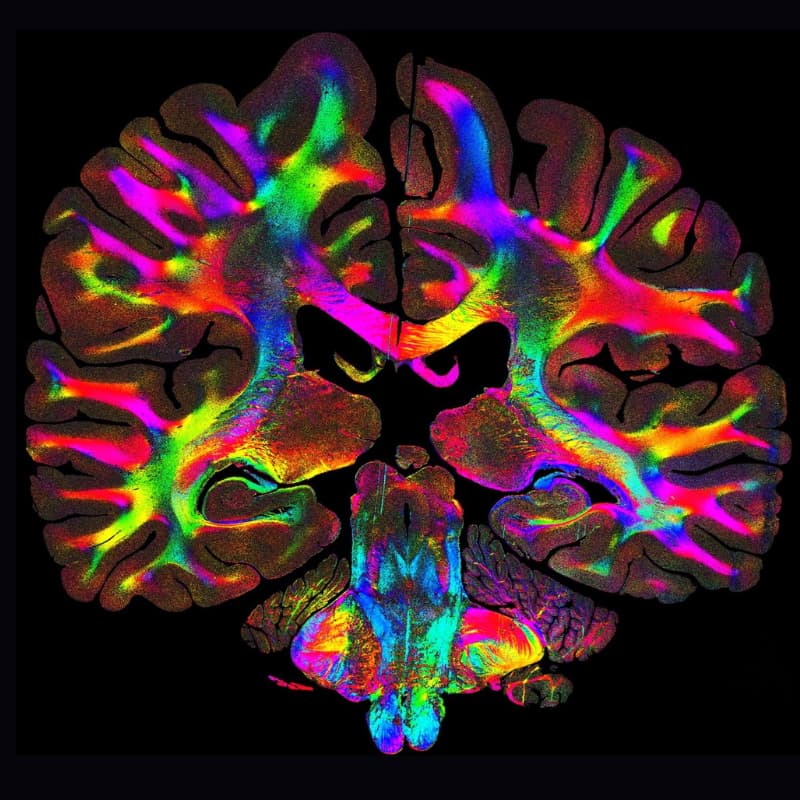

The result is a color-coded map of all the fiber orientations. Each color represents a different angle, providing a detailed view of the fiber bundles connecting the different brain regions. In neurodegenerative diseases like Parkinson’s, the orientation of these fibers provides clues about disease progression and which areas are involved.

A scan of a brain section with the colored fibers. © Georgiadis et al., Nature Communications 16:9572, 2025